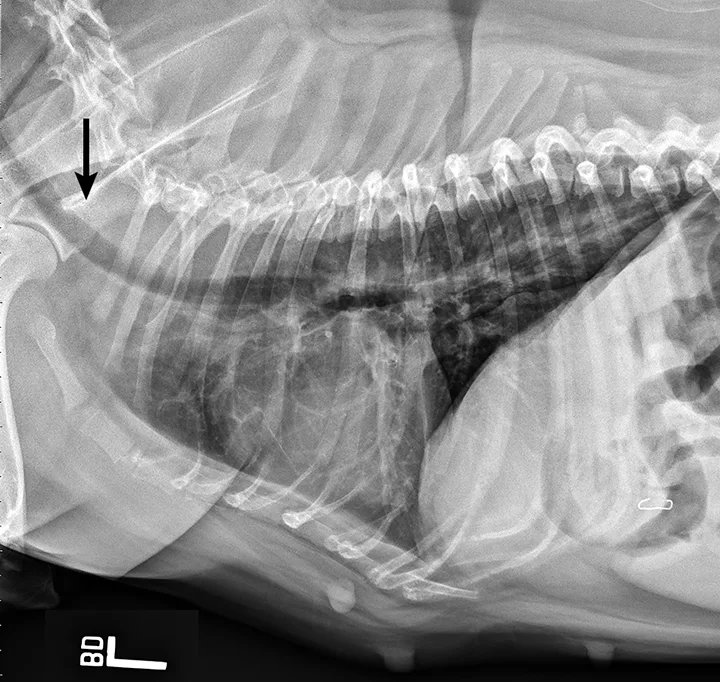

Thoracic radiographs reveal a mildly hypoplastic trachea and no evidence of aspiration pneumonia (Figure 1). A lateral cervical radiograph shows an elongated, thickened soft palate partially obstructing the laryngopharynx and nasopharynx (Figure 2). Airway examination confirmed the elongated soft palate obstruction and tonsillar eversion (Figure 3). Everted laryngeal saccules are also present. Brachycephalic obstructive airway syndrome (BOAS) is diagnosed. Folded flap palatoplasty, laryngeal sacculectomy, and alarplasty are recommended after improvement in airway swelling associated with the acute episode.

FIGURE 1

Left lateral thoracic radiograph demonstrating mildly hypoplastic trachea (arrow)